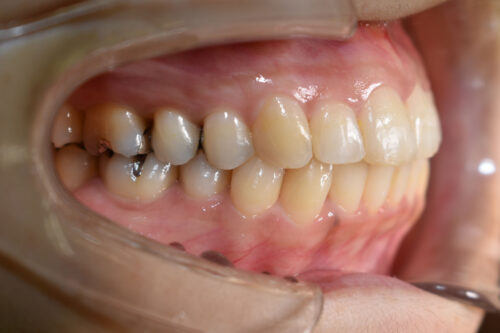

ワイヤー矯正治療9か月後です。

全額矯正治療 88万円、3~4週に一回来院

歯科矯正用アンカースクリュー(デュアル・トップオートスクリュー)上顎左右2本(25000円x2本分 提携医院にて)

ワイヤー期間 9か月, 13回来院

マウスピース型カスタムメイド矯正歯科治療を用いた矯正歯科治療装置を利用した矯正治療 3か月間 33000円、